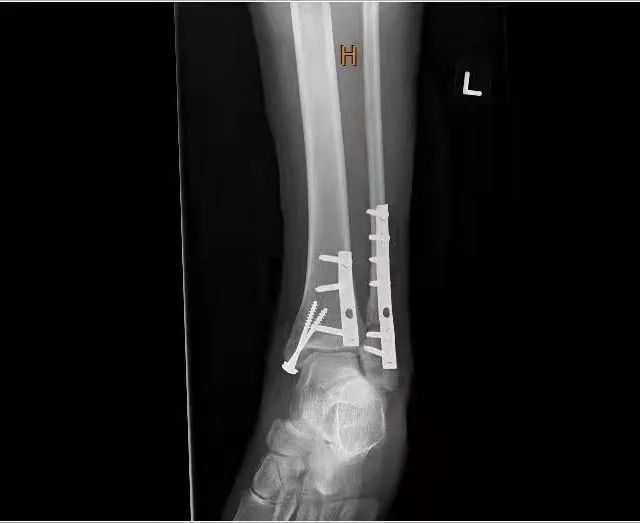

受傷三周后,我終于做了手術(shù),醒來的時(shí)候,我已經(jīng)在術(shù)后觀察室了,醫(yī)生在我腳踝的內(nèi)外側(cè)各放了一塊鋼板和幾枚鋼釘,還給我辦了植入證明。

術(shù)后X光檢查可見鋼板和釘。